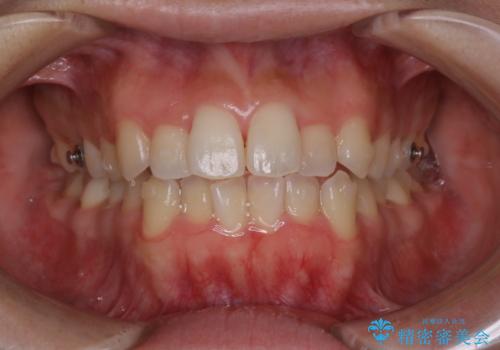

オープンバイト(開咬)を非抜歯インビザラインで治す

- 上下のがたつきを気にされてご相談にいらした患者さまです。

症状としてはオープンバイト(開咬)があり、舌癖も見られました。

オープンバイトの方への治療は、通常抜歯を行いワイヤーによる矯正治療を行うことが多いですが、今回はインビザラインの特性を生かし、非抜歯にて綺麗な歯並びを作ることが出来ました。